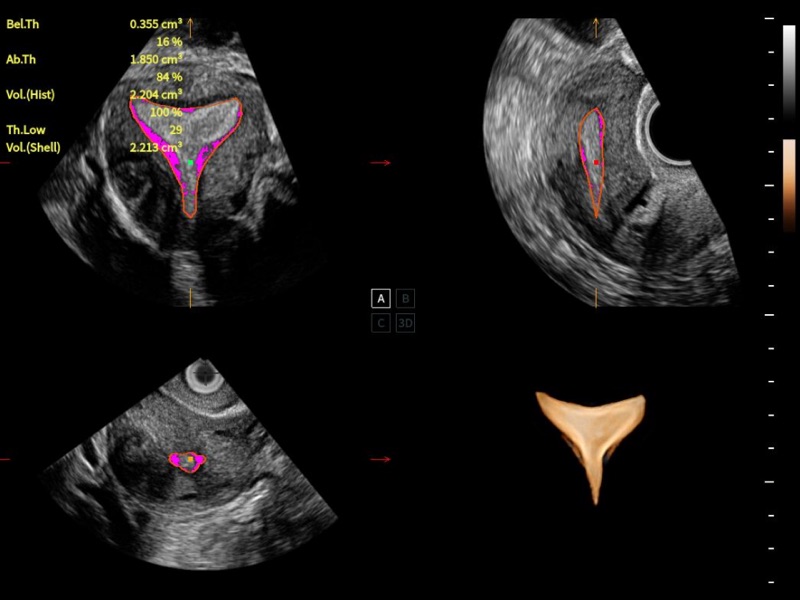

夢(mèng)溪?P80以“關(guān)愛女性”為基石,提供全方位的解決方案,量身定制以滿足女性的健康需求,涵蓋婦科、生殖健康檢查、產(chǎn)前篩查及產(chǎn)后康復(fù)等領(lǐng)域。